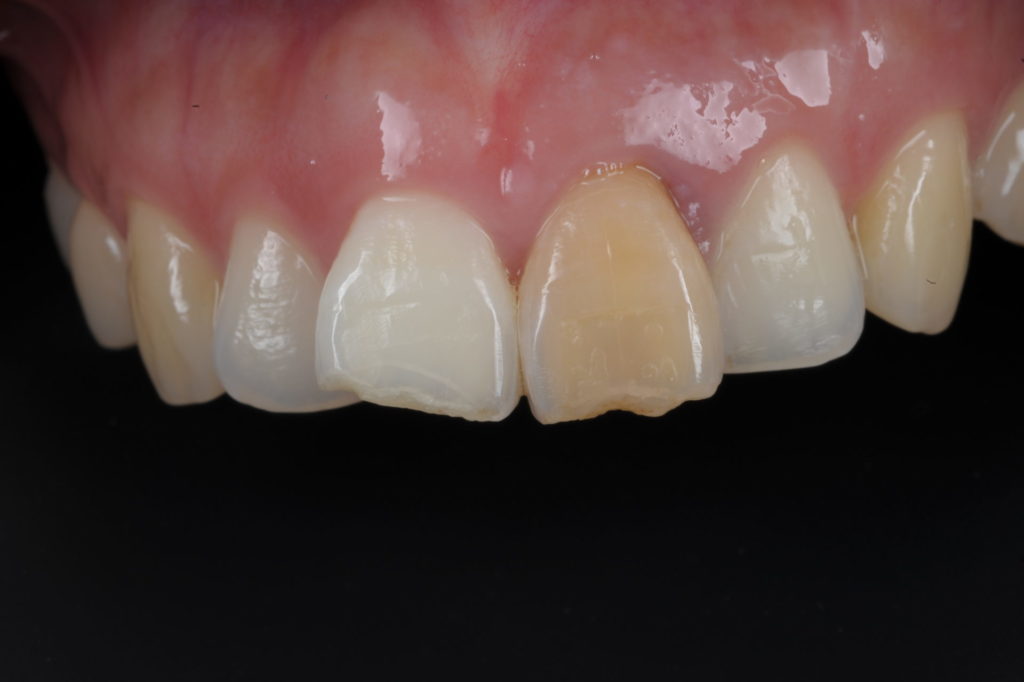

神経が死んでしまった歯の色が気になります。

2019年10月15日

こんにちは北戸田COCO歯科です 先日の台風は雨風がとても強く不安な夜でしたね。幸い、この辺りは何事もなくでしたが、被害にあわれた方も…[read more]